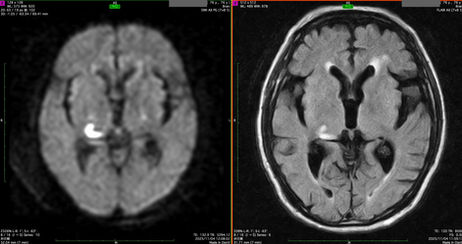

脳梗塞による視野障害

本日、市内の眼科医院から紹介された患者さんは、「左下同名1/4盲」という視野障害があり、脳MRIで右側の視放線から外側膝状体の一部にDWIという撮像方法で急性期の脳梗塞が示された。写真の白く強く光ったように見える部分である。 眼科の視野計測だけでは、脳梗塞の判断はつかないが、MRIを撮って初めて診断がつき、脳梗塞の治療を始めることができた。